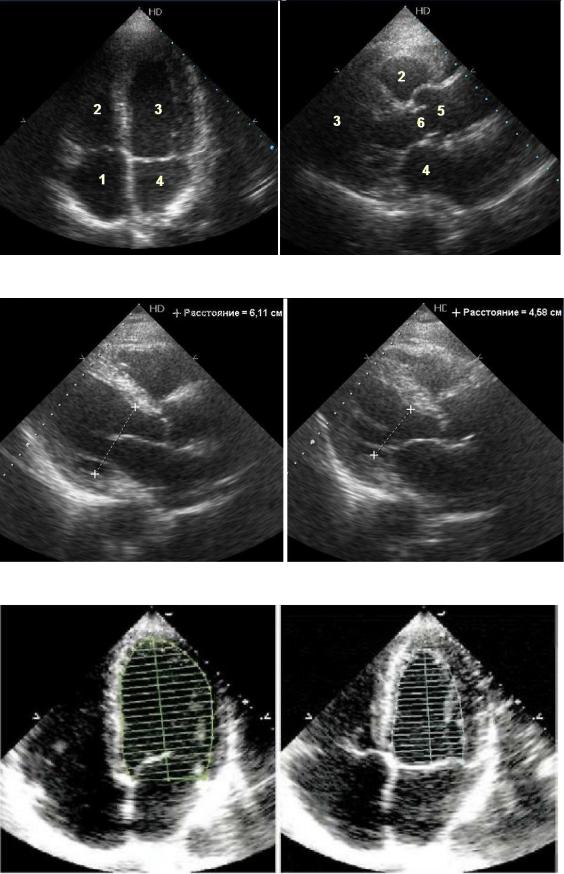

2.Ультразвуковая анатомия сердца (рис. 2).

3.Систолическая функция левого желудочка (рис. 3 и 4).

Рис. 2.

Рис. 3.

Рис. 4.